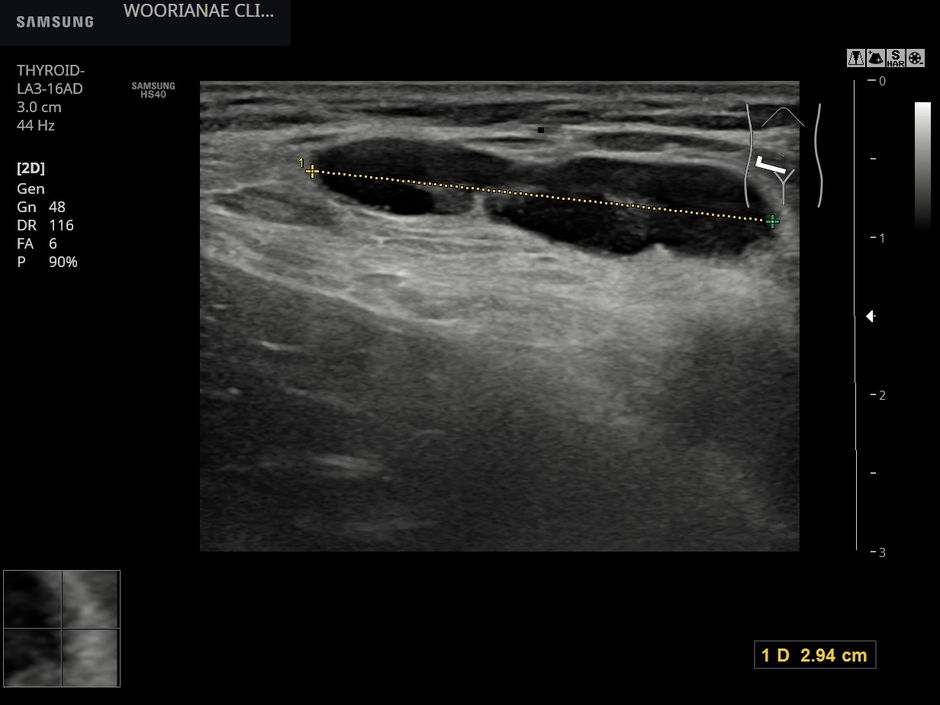

내원 전일 서혜부 초음파에 대해 문의하였었음... 림프절이 만져지는 임상상황이 많아서 확답을 줄수는 없고... https://blog.naver.com/ejercicio/221037914891 다음날 방문 30대 중반 여자 오래 전부터...